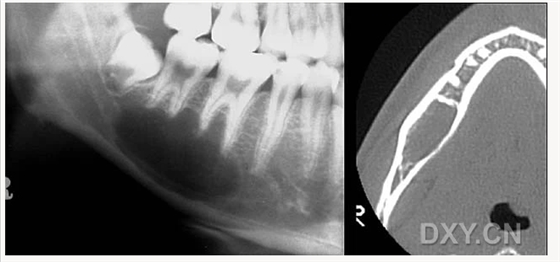

頜骨骨折